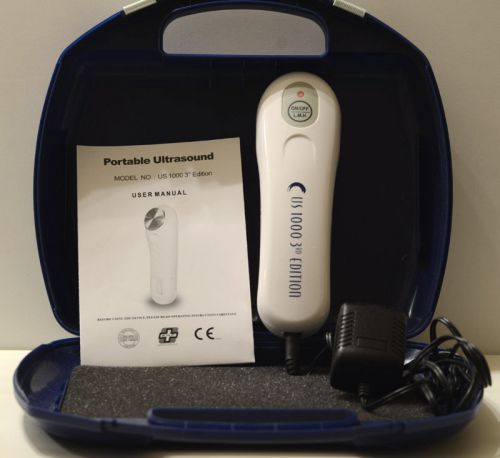

US Pro 1000 3rd Edition Portable Ultrasound Therapy Unit